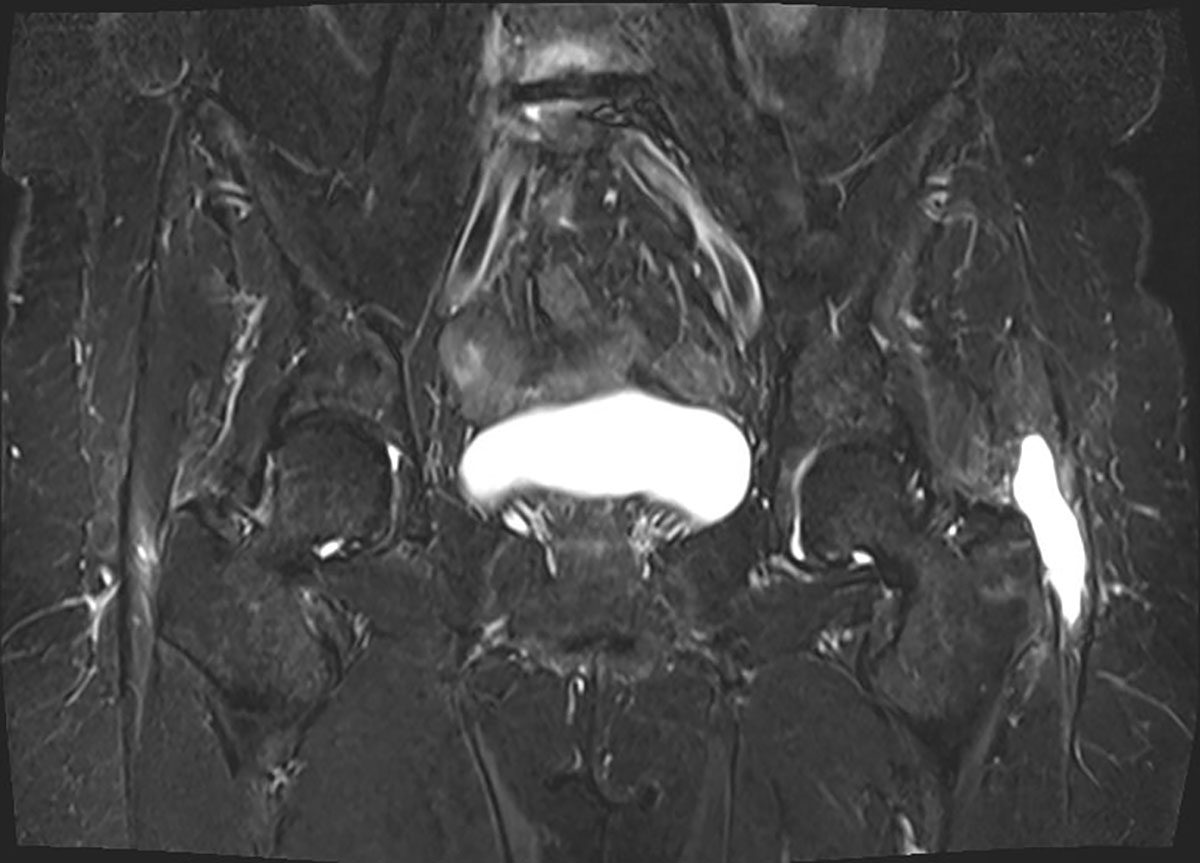

Neben einer typischen Anamnese und klinischen Untersuchung stellt die Bildgebung das entscheidende diagnostische Mittel zum Nachweis einer glutealen Insuffizienz dar. Konventionelle Röntgenbilder (Hüftübersichtsaufnahme a.-p., axiale Projektion des proximalen Femurs, ggf. Faux-Profilaufnahme) dienen zum Ausschluss ossärer Differentialdiagnosen. Bei einliegender Hüft-TEP muss auf mechanische Ursachen wie Lockerung und Komponentenfehlpositionierungen (Drehzentrum der Pfanne, Femur-Offset, Komponentengröße) geachtet werden. Bei nativem Gelenk können peritrochantäre Sehnenansatzverkalkungen oder osteophytäre Ausziehungen als Ausdruck degenerativer Veränderungen erkannt werden. Sonographisch bietet sich die Möglichkeit, ansatznahe Rupturen zu beurteilen, die Sensitivität wird vereinzelt als gut beschrieben. Als Goldstandard gilt die MRT des Beckens. Hierbei gelingt es, durch Wahl geeigneter Sequenzen und Schichtungen Tendinopathien und Rupturen hoch sensitiv nachzuweisen. Bei einliegender Hüft-TEP sind zur genauen Beurteilung der Glutealmuskulatur artefaktreduzierte Sequenzen (z. B. MARS) nötig.